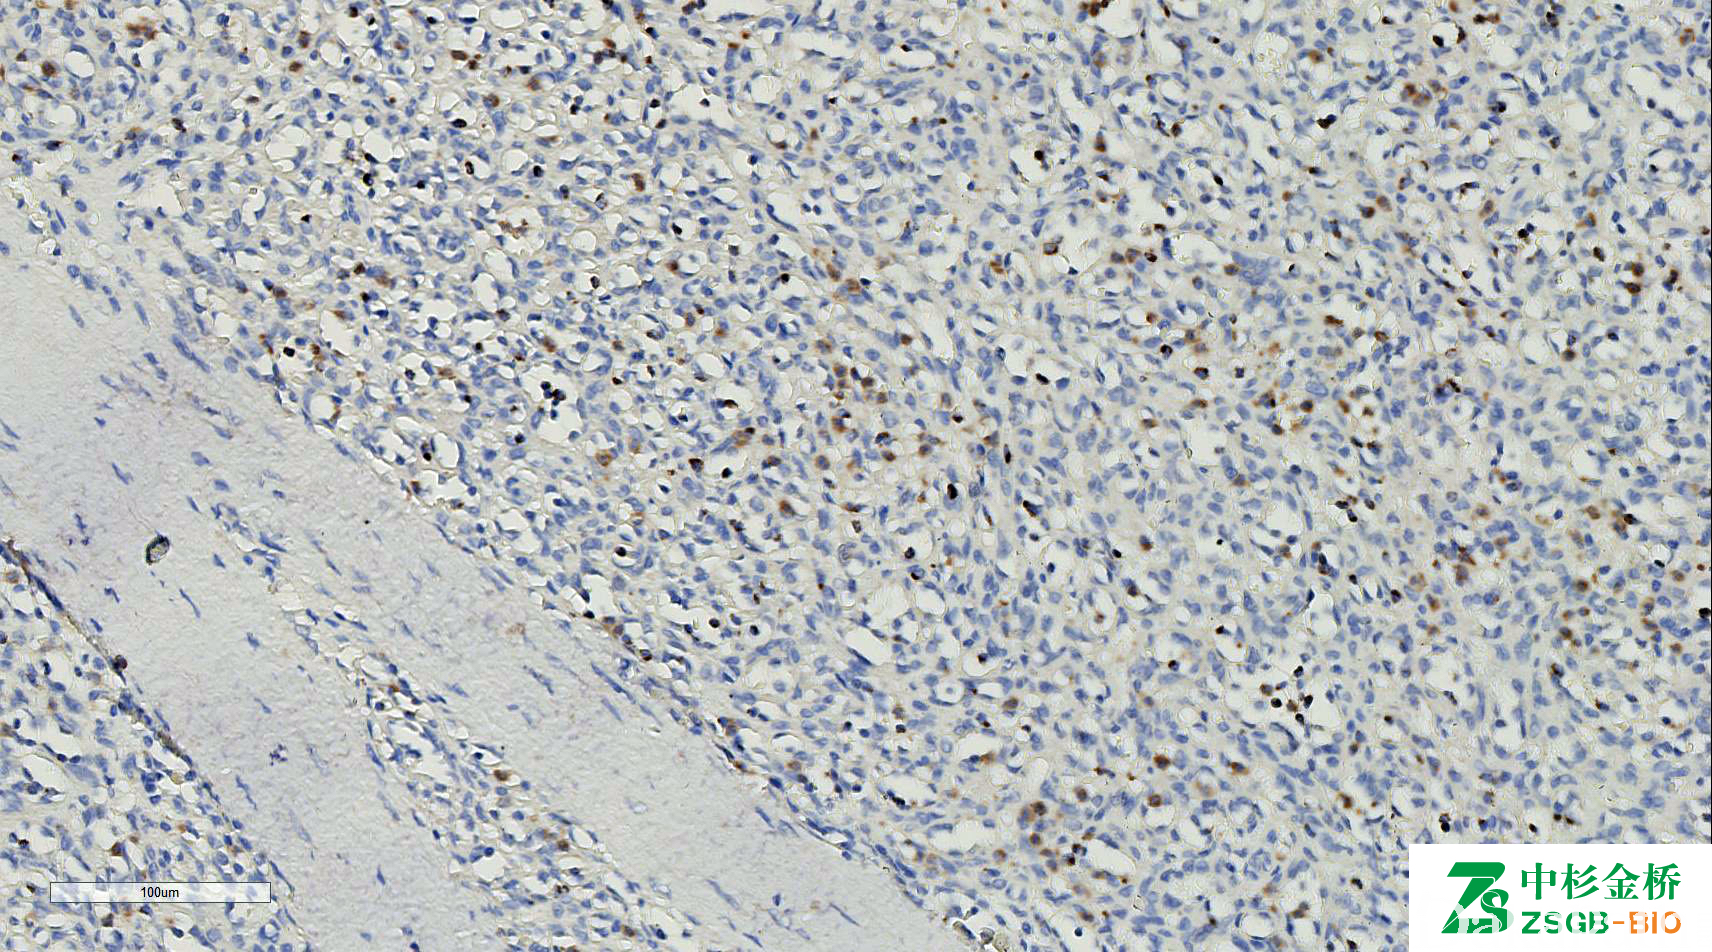

T 细胞胞浆抗原,标记细胞毒性淋巴细胞胞浆蛋白,以非活化状态的细胞毒细胞为主,在细胞毒性 T 细胞或 NK 细胞来源的淋巴瘤中常阳性表达。

信号定位: 胞质(颗粒状)